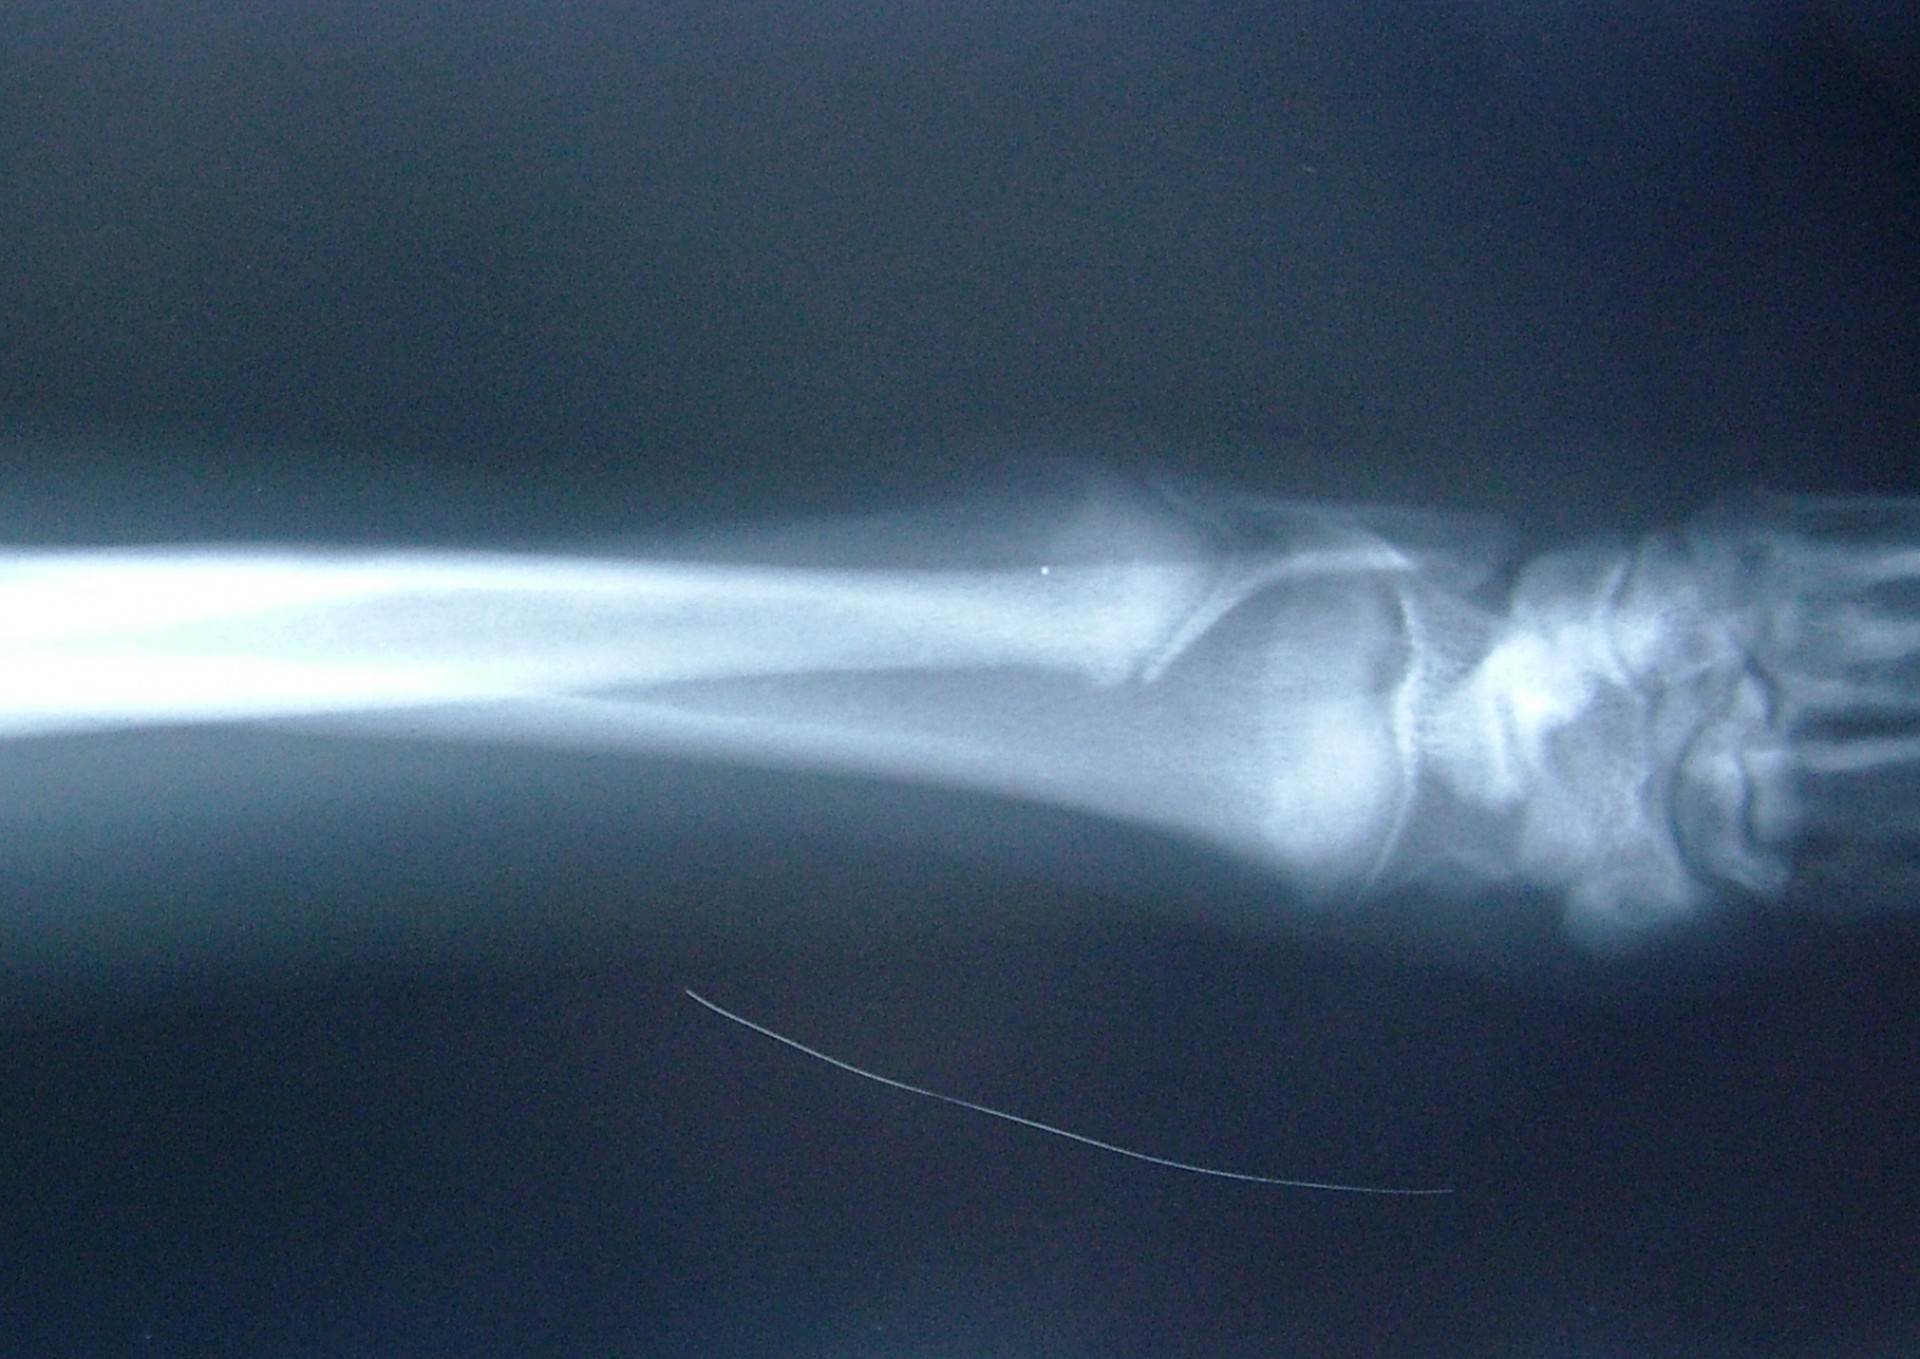

A könyökcsont növekedési zónájának záródása (short ulna)

A könyökcsont alsó epiphysisének lezáródása (short ulna) az alkar kifelé történő görbülését eredményezi (valgus állás). A klinikai tünetek (végtagdeformitás) mindig fokozatosan, lassan alakulnak ki, sok esetben a növekedési zóna lezáródásához vezető trauma nem igazolható. Az állat a lábát az elülső lábtőízület alatti területen kifelé fordítva tartja.A fizikális vizsgálat során fájdalom nem tapasztalható és az altatásban történő vizsgálat során a végtag deformitása nem szüntethető meg. A kiegészítő RTG vizsgálattal a könyökcsont alsó növekedési zónájának záródása egyértelműen igazolható. Ezek alapján a betegség az elülső lábtőízület lazaságától (carpal laxity) egyértelműen elkülöníthető. Mivel a végtagállási hiba már kölyök korban megjelenik fontos annak elkülönítése is, hogy örökletes úton (X-láb) vagy a növekedési zóna lezáródása következtében alakult ki a valgus állás.